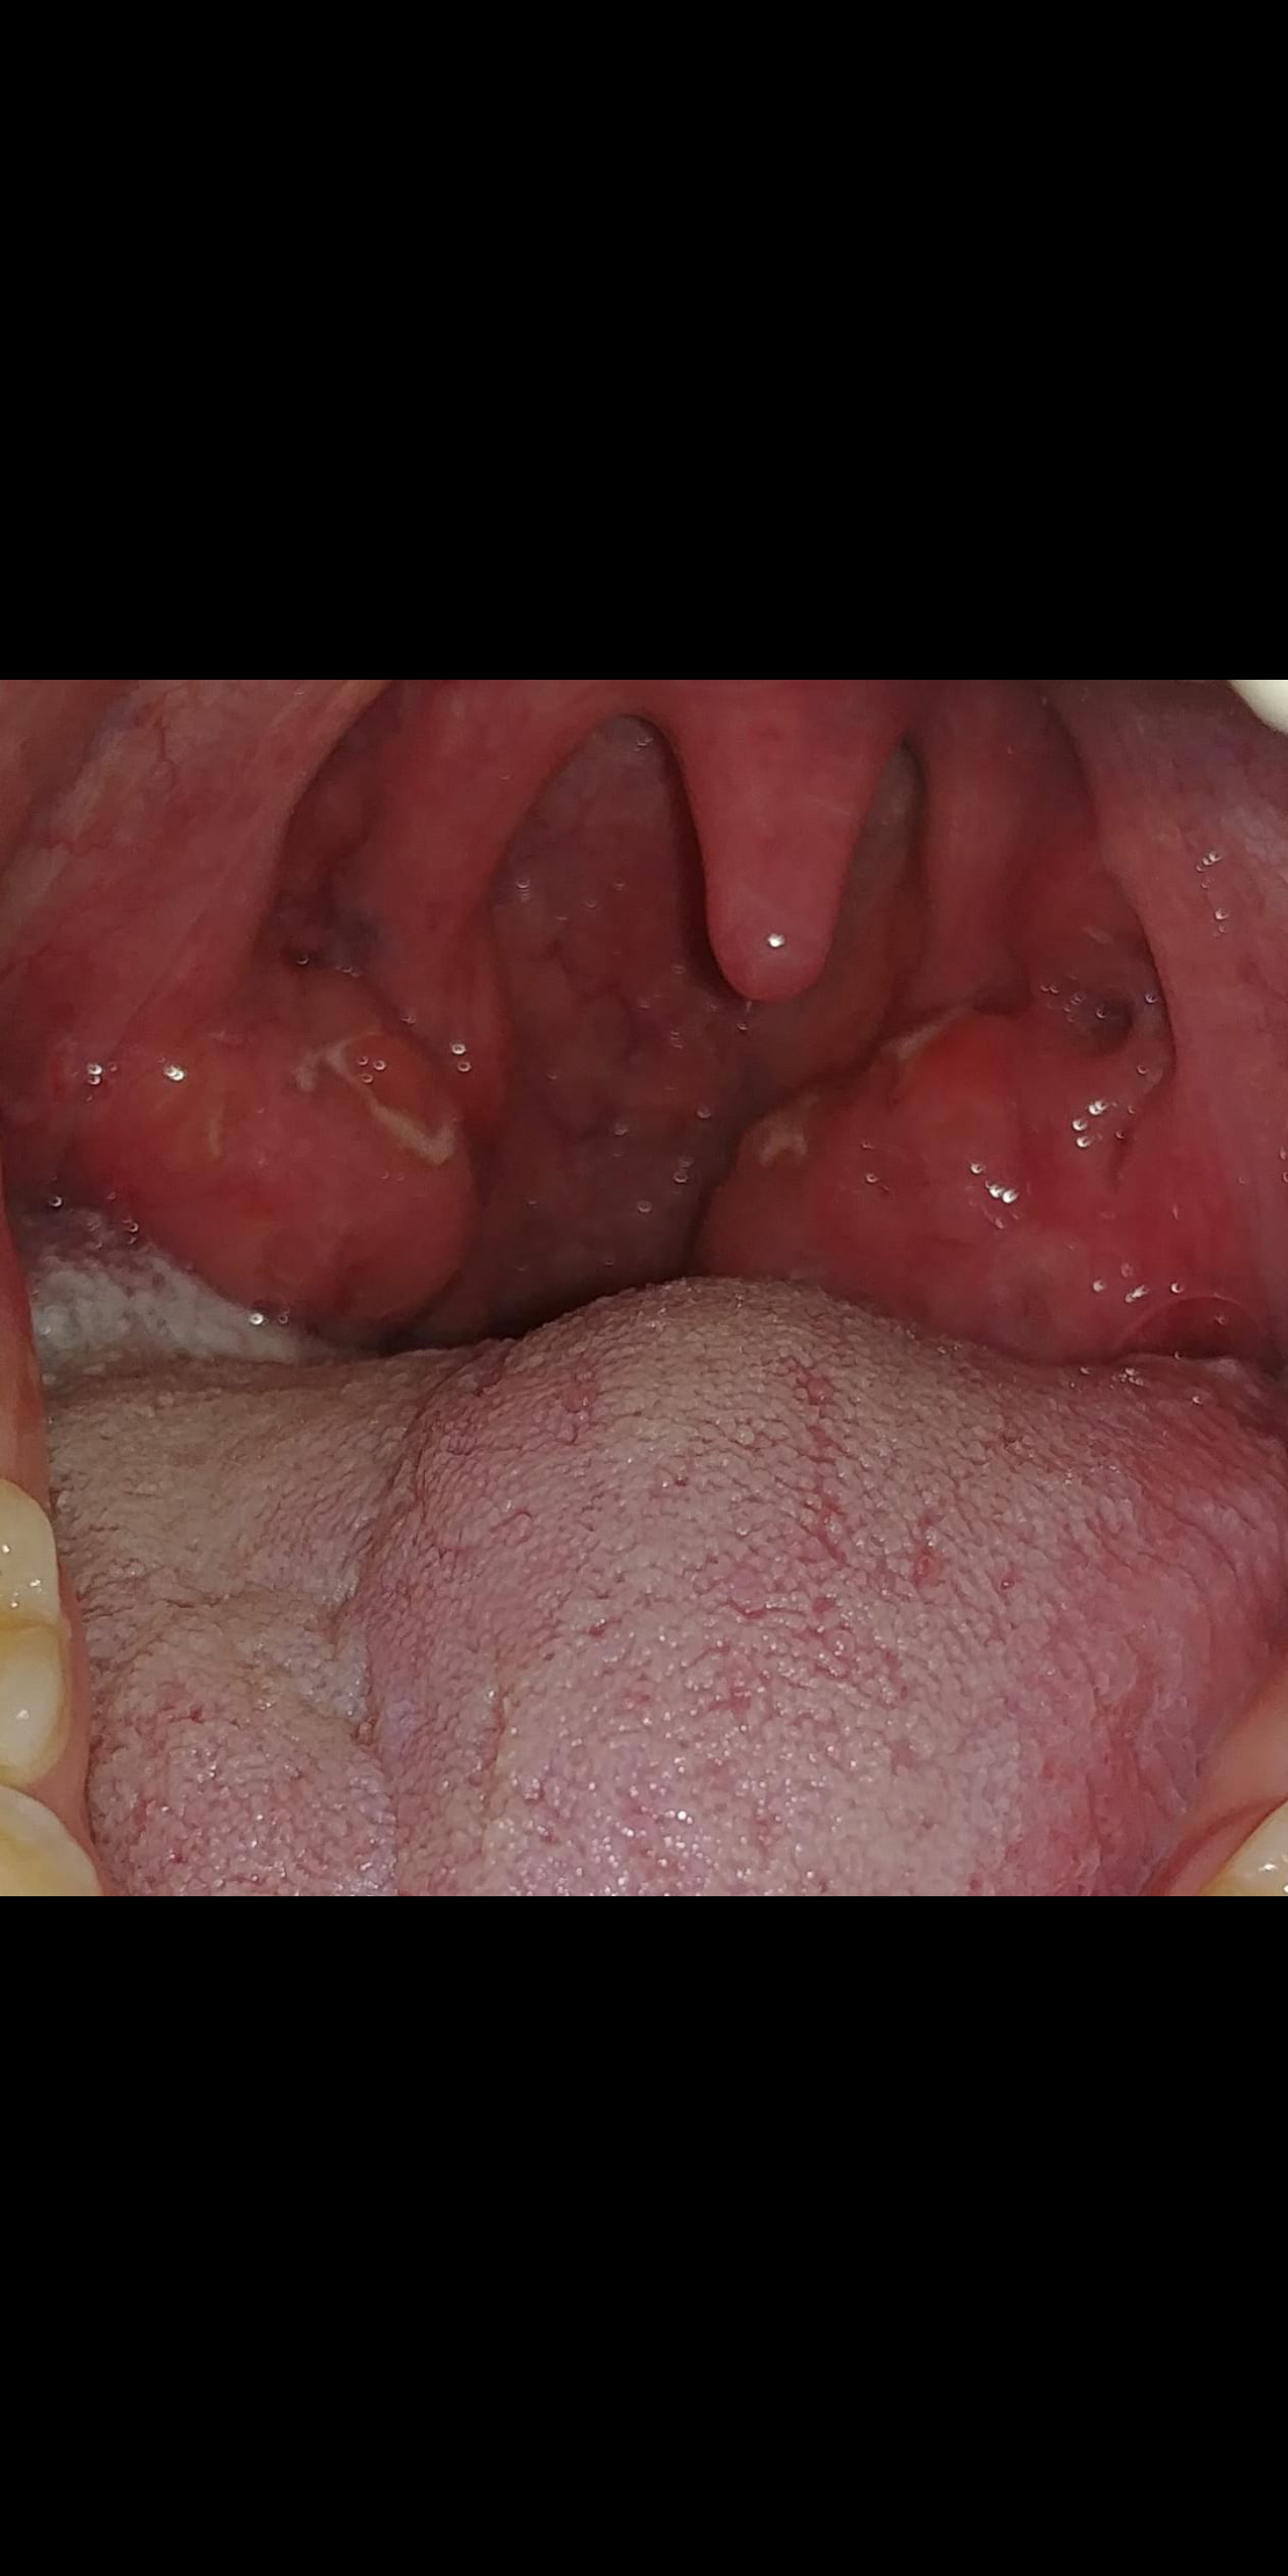

A la 6ta semana me dio una infeccion en la garganta la cual se curo aprox a los 10 dias( la infeccion ocurrio el 28 de enero), a la fecha esta un poco inflamada aun y he leiod que las amigdalas son ganglios linfaticos, y he leido que el vih ocasiona inflamacion de ellos:(